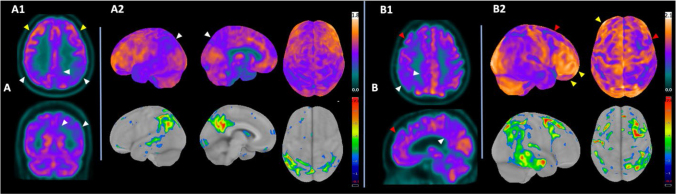

Abstract Image